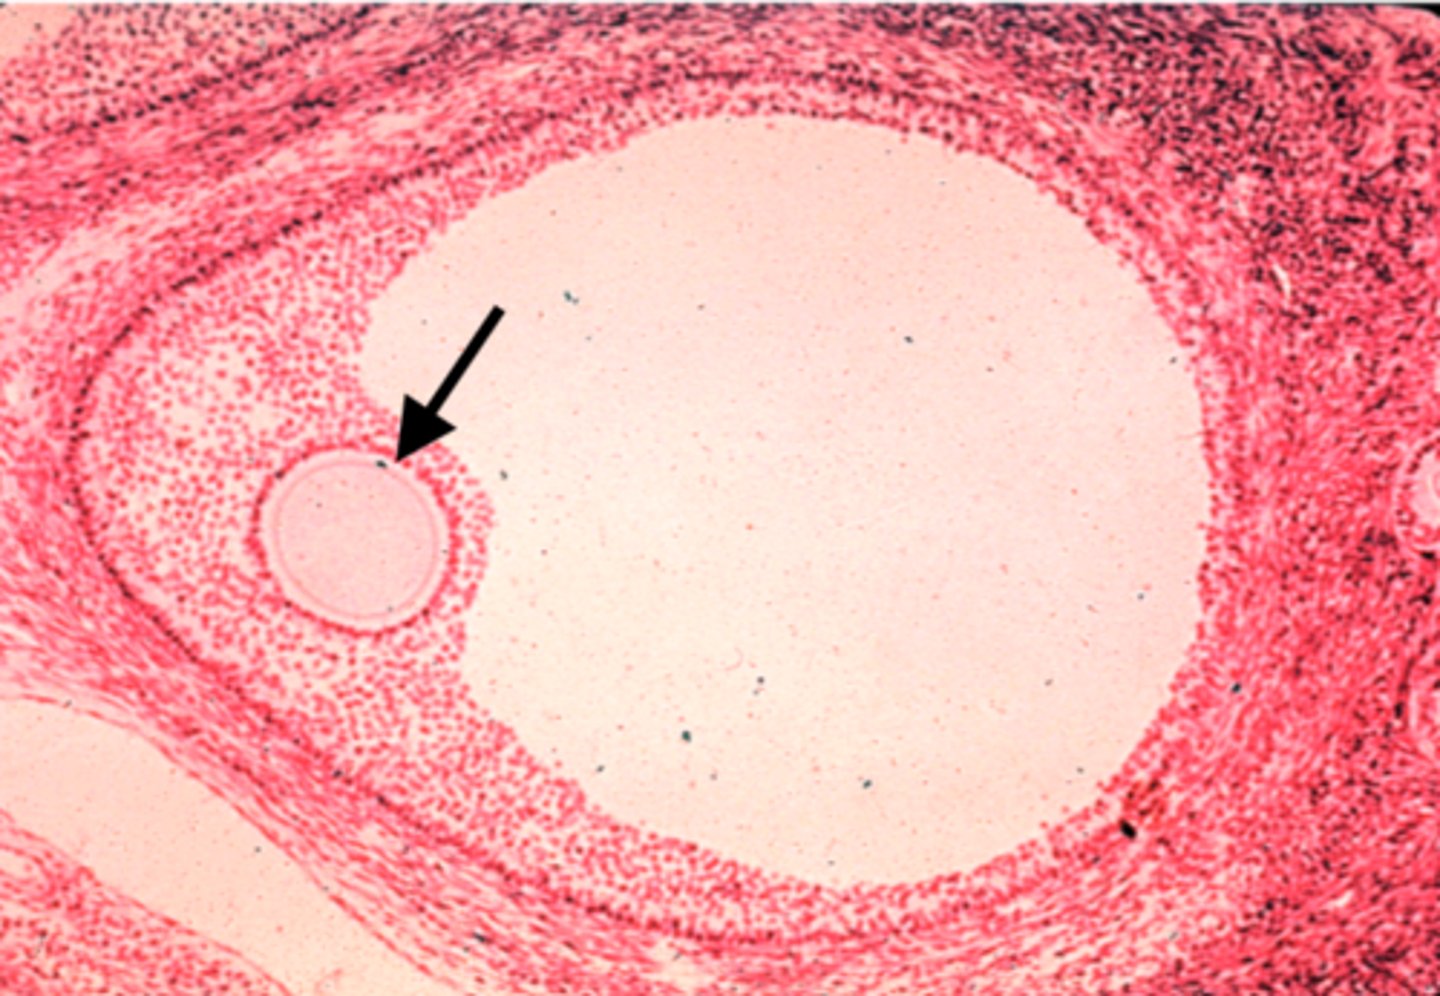

Epididymis

What is this?

Vas deferens

What is this?

Ovary

What is this?

egg

What is this?